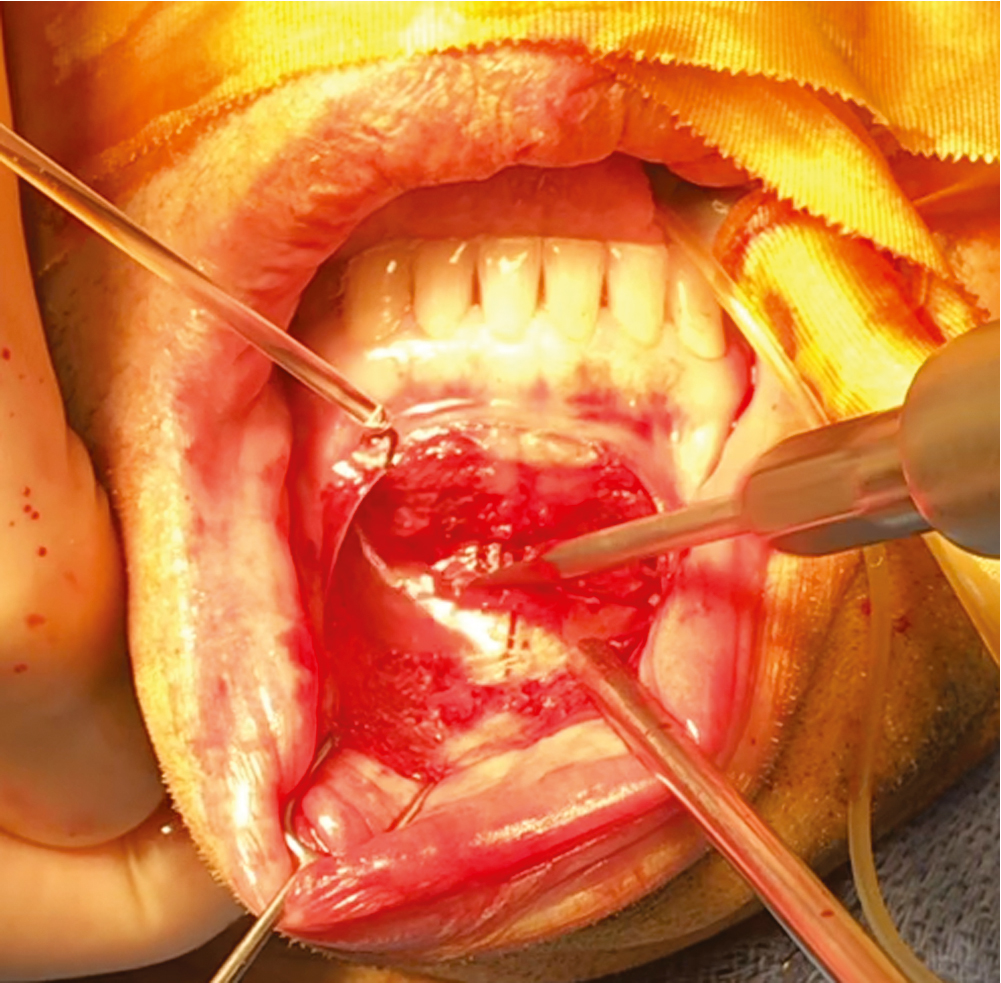

- •

A periosteal elevator is then used to dissect from the incision to the inferior border of the mandible in an inferior direction. Once the inferior border has been identified, the periosteal elevator can be used to dissect laterally in the subperiosteal plane along and parallel to the inferior aspect of the mandible. Because the mental foramen is 14 mm superior to the inferior mandibular border and the widest Obwegeser periosteal elevator is 10 mm wide, this dissection can be done rapidly and blindly without worry of hitting the mental nerve as long as the surgeon keeps the elevator flush with the inferior border of the mandible. We refer to this region as a dissection “hot lane,” meaning the dissection can be done very quickly without risk of injury to the mental nerve. Once this dissection has been done bilaterally, careful superior elevation easily identifies the mental nerve ( Fig. 27.2 ).

Fig. 27.2

(A) The Obwegeser periosteal elevator is placed such that the edge is adjacent to the inferior border of the mandible. The location is confirmed by palpation, and the surgeon can advance the elevator laterally in a subperiosteal plane to dissect the pocket rapidly. As long as the elevator’s inferior edge is congruent with the inferior border of the mandible, there is little risk of injuring the nerve, and the dissection can be done blindly. (B) The widest of the Obwegeser periosteal elevators is 10 mm. The distance from the inferior border of the mandible to the mental foramina has been shown to be 14.61 mm. Given that there is a 5-mm safety margin, a rapid blind subperiosteal dissection can be performed as long as the edge of the elevator hugs the inferior edge of the mandible.